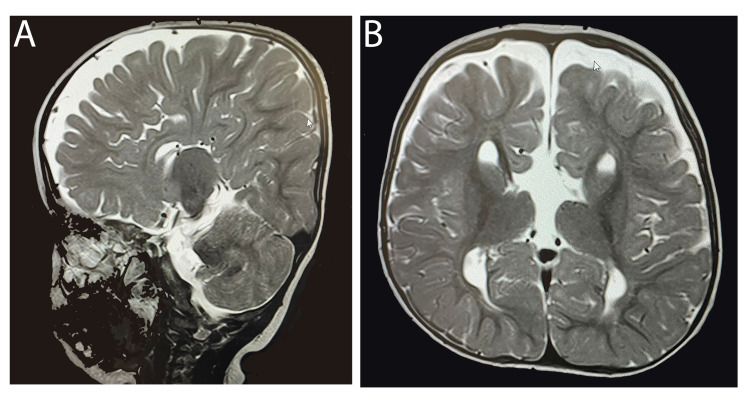

一名 14 個月大的女童,有全身發(fā)育遲緩、畸形特征(眼距過遠、眼球突出、上瞼下垂、小頜畸形)和弱視病史,被轉(zhuǎn)診至佳學(xué)基因遺傳病罕見病基因檢測案例協(xié)作單位。就診原因是言語和語言發(fā)育遲緩。 她的父母是一級近親,被診斷患有雙側(cè)重度至極度SNHL,并在 9 個月大時安裝了雙側(cè)助聽器。 然而,在隨訪中沒有發(fā)現(xiàn)使用助聽器有明顯的好處。 磁共振成像 (MRI) 顯示胼胝體有效發(fā)育不全(圖 1)。 此外,全外顯子組測序顯示 LRP2 基因突變,證實了 DBS 的診斷。 在 18 個月大時,她的智商測試成績?yōu)?75 分。

An external file that holds a picture, illustration, etc.

Object name is cureus-0014-00000021063-i01.jpg

病例 1 的 MRI:(A) 矢狀切面 (B) 冠狀切面顯示胼胝體有效發(fā)育不全